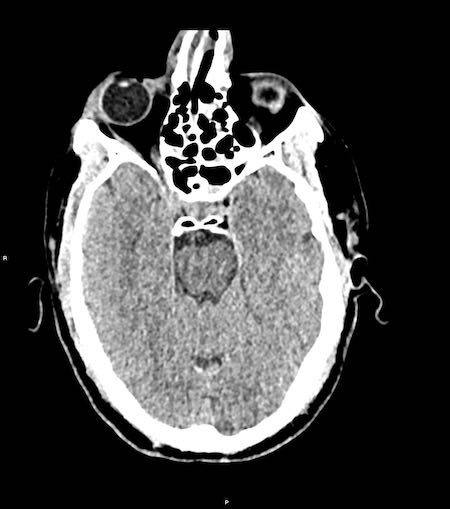

Bé trai 11 tuổi ngã khỏi xe đạp, có thể do cơn co giật động kinh.

Bé đập đầu vào lề đường.

Mức độ ý thức giảm với điểm EMV là 2-4-3.

Bệnh nhân biểu hiện nhịp tim chậm, tăng huyết áp, tư thế bất thường và đồng tử phải giãn không phản xạ ánh sáng — tất cả đều là dấu hiệu của thoát vị não và tăng áp lực nội sọ.

Hình ảnh CT

- Ghi nhận khối xuất huyết hình thấu kính vùng thái dương-đỉnh

- Khối xuất huyết bị giới hạn bởi các đường khớp sọ

- Gãy xương sọ kèm theo

- Dấu hiệu xoáy (swirl sign) cho thấy sự thoát mạch của máu vào trong khối tụ máu. Dấu hiệu này đại diện cho máu tươi chưa đông (giảm tỷ trọng) bao quanh bởi máu đã đông (tăng tỷ trọng hơn).

- Thoát vị dưới liềm não theo chiều ngang và thoát vị móc hải mã.

Bệnh nhân sau đó được phẫu thuật mở hộp sọ và động mạch màng não giữa bị rách đã được đốt cầm máu.

Kết quả lâm sàng tốt.